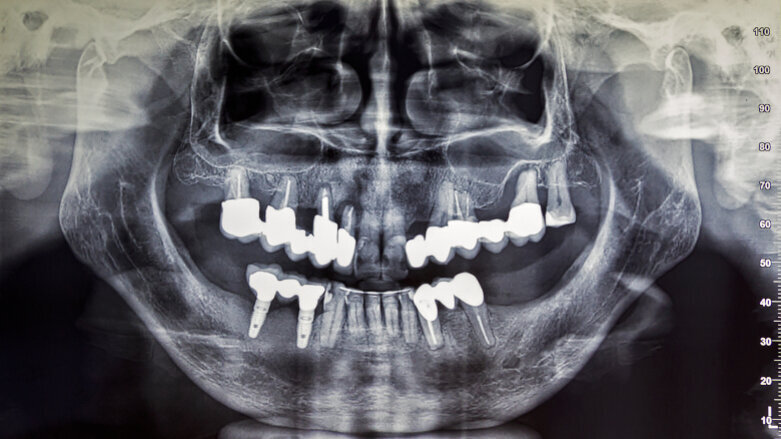

A recent study has found that reducing the patient radiation to 20% of the manufacturer-recommended protocol does not compromise the CBCT image quality. (Image: Massimo Cattaneo/Shutterstock)

MALMÖ, Sweden: Radiographic diagnostics are widely used in healthcare as they provide diagnostically important information that can help improve treatment outcomes. For example, a CBCT scanning protocol is a valuable examination tool in oral and maxillofacial radiology and is readily available in dental offices because of its ease of use. However, a CBCT scan produces a relatively high radiation dose compared with other scanning protocols, and new research has shown that its effectiveness remains unchanged after reducing the radiation dose to one-fifth of the manufacturer-recommended level.

In the study, 34 adult patients referred for CBCT imaging of the temporomandibular joint underwent two examinations with two scanning protocols: a manufacturer-recommended protocol and a low-dose protocol where the tube current was reduced to 20% of the recommended protocol. The researchers noted that manufacturer-recommended exposure settings for the CBCT scanners vary widely and may result in varying amounts of radiation doses.

After evaluating the visibility of temporomandibular joint anatomic structures and image quality, the radiologists who were tasked to analyse the images concluded that both the low and high dose images yielded diagnostically comparable results. Therefore, the findings suggest that high image quality is not necessary for all clinical situations and that dental professionals should reduce the recommended patient radiation dose provided that it does not affect diagnostic outcomes. They noted that this is especially important when treating younger patients who are at a higher risk from radiographic exposure than adults owing to the radiosensitivity of their developing tissues.